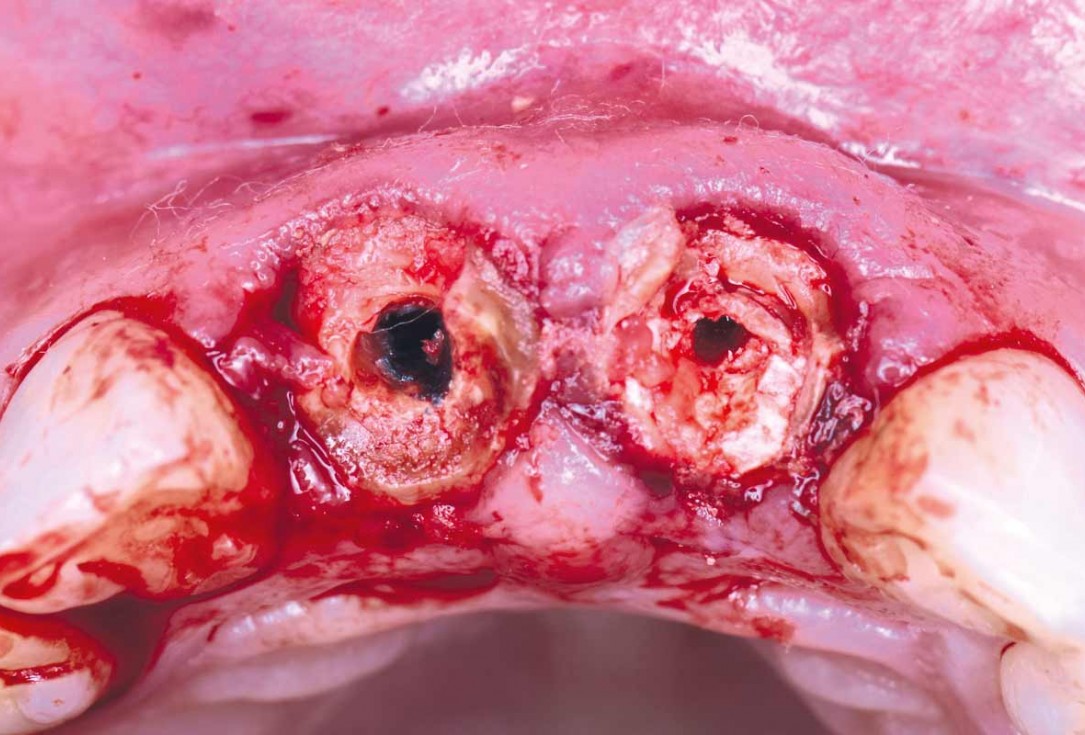

01/22 - Initial clinical situation - Central incisors with dental destruction and periapical pathologycerabone® and mucoderm® for immediate implantation in the aesthetic area - Dr. D. Robles

02/22 - Initial clinical situation - Central incisors with dental destruction and periapical pathologycerabone® and mucoderm® for immediate implantation in the aesthetic area - Dr. D. Robles